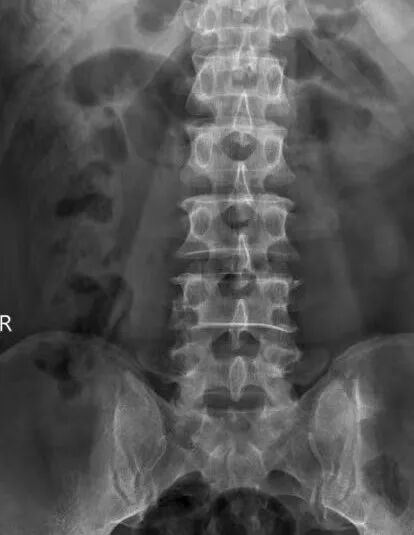

患者江先生,56岁,因外伤4椎体压缩性骨折。为了最大限度减少对患者的创伤,加快其康复,术前科室进行认真讨论,查阅资料,观看手术视频,制订详细的手术计划,于929日在全麻下行微创小切口脊柱后路钉棒系统内固定术治疗腰4椎体压缩性骨折,术后复查X线提示腰椎高度恢复,内固定位置正常。

姚主任介绍道,传统椎弓根内固定植骨融合术采用切开皮肤,剥离肌肉,显露椎体结构后,植入椎弓根螺钉固定,存在创伤大(约10厘米)、椎旁肌肉剥离广泛、术中出血多(一般出血约300毫升)、术后切口引流量大(一般约200毫升)、术后切口疼痛、恢复期长等。而微创经皮椎弓根钉棒内固定植骨融合术因其手术创伤小(约2厘米),术中出血少(约20毫升),不剥离椎旁肌肉,术后切口无需引流,无术后切口疼痛,可早期下地进行功能恢复,是近年来发展起来的新技术,也是目前微创治疗腰椎滑脱、胸腰椎骨折、椎管狭窄、肿瘤等脊柱疾病的一种先进手术方式。经皮椎弓根钉棒系统内固定术微创技术,对手术技术要求比传统手术方式更高,术前需要非常周密的计划,根据患者的影像资料做非常精确地测量和定位,更需要手术医生具有非常娴熟的开放椎弓根钉棒系统内固定技术及经皮椎弓根穿刺技术。